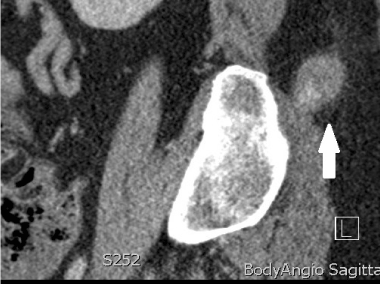

A 60 year old female presented with increasing right lower back pain and swelling at the site of a BMAT that was performed six weeks prior. The results of this BMAT were consistent with myelodysplastic syndrome. Her past medical history included large cell lung carcinoma 8 years prior that was treated with left lobectomy and chemotherapy. On presentation her platelet count was 30 ×109/L and her haemoglobin level was 92g/L. An ultrasound demonstrated a hypoechoic cavity measuring 37 × 20 × 23mm with internal vascular flow favouring a pseudoaneurysm. A computed tomography angiography (CTA) confirmed a pseudoaneurysm of a lumbar artery branch overlying the right iliac bone (Figures 1 and 2). It was planned to treat this with thrombin injection. In consultation with the haematology team, a unit of platelets was given which brought her platelet count to 50 × 109/L. During the procedure, the interventional radiologist found the pseudoaneurysm to be largely thrombosed and so it was treated with ultrasound guided compression alone with good immediate result. The patient was discharged and an ultrasound scan performed one week later showed a completely thrombosed pseudoaneurysm with no internal flow.

Figure 1. Computed tomography angiography: axial view of the lumbar artery pseudoaneurysm.